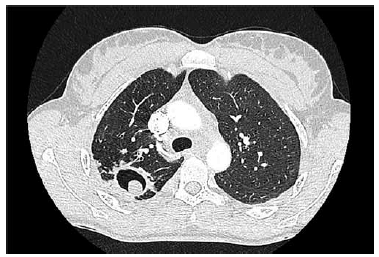

Paciente do sexo masculino com 53 anos de idade procura pneumologista devido ao surgimento de hemoptise há, aproximadamente, 3 meses. Relata que os episódios têm sido mais frequentes e com maior volume de sangue eliminado. A tomografia de tórax do paciente é apresentada a seguir.

A melhor conduta terapêutica para esse paciente é